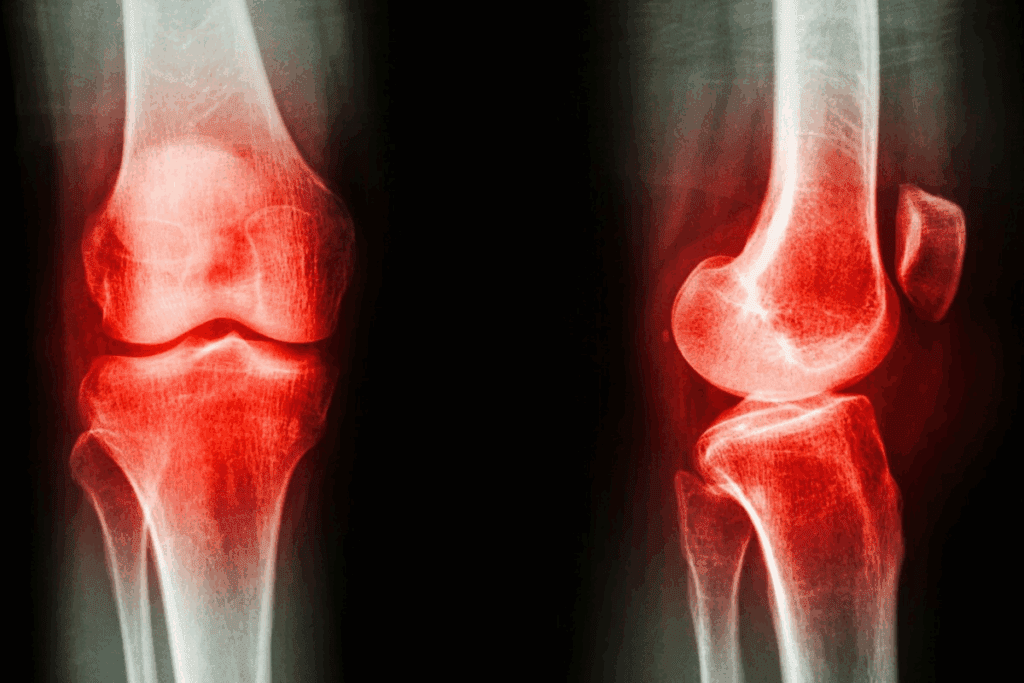

Osteoporosis is called a “silent disease” because it quietly weakens bones. It happens without symptoms until a bone breaks. It affects bone density, making bones more likely to break.

Osteopenia and osteoporosis both have low bone mass. But osteopenia is less severe. Osteoporosis means bone density is much lower, raising the risk of breaks.

Early diagnosis through bone density tests is key. It helps tell osteopenia from osteoporosis. This allows for early action to stop bone breaks.